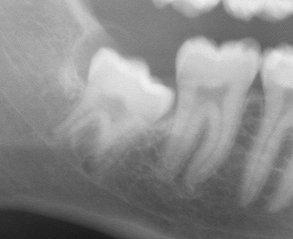

Buccal Bifurcation Cyst

Inflammatory cyst with uncertain pathogenesis

Develops on BUCCAL aspect of the mandibular 1st permanent molar (2nd molar) – PARTIALLY ERUPTED

Pushes the crown buccally and the roots lingually (develops below CEJ)

Occurs in avg age of 10

Symptoms: Tenderness, swelling, or fout tasting discharge